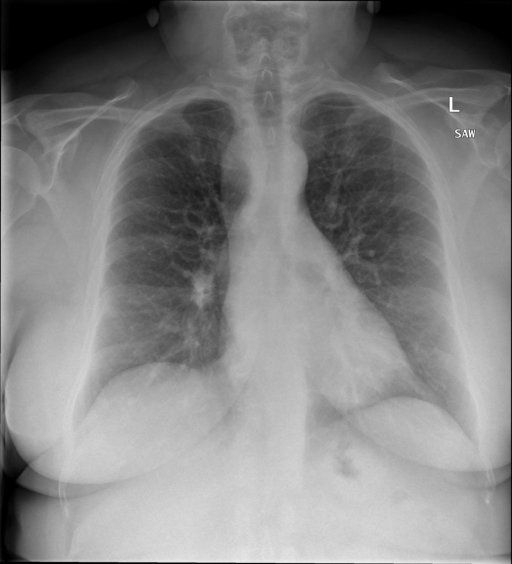

# 本文贡献  - 借助ChatGPT以及公开的数据集,我们构造了一个`X光影像-诊断报告`对的医学多模态数据集; - 我们将构建的中文胸部X光片诊断数据集在[VisualGLM-6B](https://github.com/THUDM/VisualGLM-6B)进行微调训练,并开放了部分训练权重用于学术研究; # 数据集 - [MIMIC-CXR](https://physionet.org/content/mimic-cxr-jpg/2.0.0/)是一个公开可用的胸部X光片数据集,包括377,110张图像和227,827个相关报告。 - [OpenI](https://openi.nlm.nih.gov/faq#collection)是一个来自印第安纳大学医院的胸部X光片数据集,包括6,459张图像和3,955个报告。 在上述工作中,报告信息都为非结构化的,不利于科学研究。为了生成合理的医学报告,我们对两个数据集进行了预处理,并最终得到了可以用于训练的**英文报告**。除此之外,为了更好的支持中文社区发展,借助ChatGPT的能力,我们将英文报告进行了中文翻译,并最终形成了可用于训练的数据集。 |数据集|数量|下载链接| |:-|:-|:-| |MIMIC-CXR-zh|-|-| |OpenI-zh|6,423|[诊疗报告](./data/Xray/openi-zh.json) 、[X光影像](https://pan.baidu.com/s/13GBsDMKf6xBZBSHpoWH_EA?pwd=k9sh)| # 快速上手 1. 安装环境 ```bash # 安装依赖 pip install -r requirements.txt # 国内换源安装依赖 pip install -i https://mirrors.aliyun.com/pypi/simple/ -r requirements.txt ``` 此时默认会安装`deepspeed`库(支持`sat`库训练),此库对于模型推理并非必要,同时部分`Windows`环境安装此库时会遇到问题。 如果想绕过`deepspeed`安装,我们可以将命令改为: ```bash # 安装依赖 pip install -i https://mirrors.aliyun.com/pypi/simple/ -r requirements_wo_ds.txt # 安装SwissArmyTransformer pip install -i https://mirrors.aliyun.com/pypi/simple/ --no-deps "SwissArmyTransformer>=0.3.6" ``` 2. 模型推理 CLI推理: ```python python cli_demo.py --from_pretrained checkpoints/finetune-XrayGLM-05-25-01-04 --prompt_zh '详细描述这张胸部X光片的诊断结果' ``` 更多[参数](https://github.com/WangRongsheng/XrayGLM/blob/main/cli_demo.py#L16) # 效果展示 诊断: |X光影像|诊疗报告(医生)|XrayGLM| |:-|:-|:-| ||根据X射线图像,心脏大小正常,肺部看起来很清晰。已经排除了肺炎、积液、水肿、气胸、腺病、结节或肿块的存在。该发现表明一切正常。换句话说,总体印象是胸部正常。|X光片显示,心脏大小正常。肺部没有气胸或胸腔积液的证据。骨骼结构看起来没有任何异常。总的来说,X光片表明没有发现急性心肺疾病的迹象。| ||X光图片显示没有扭曲的区域、可疑的骨质不透明度或胸腺积液。心脏大小轻微增大,但非常稳定。此外,没有气胸的证据,肺野也正常。总体来说,X光片显示没有急性心脏异常,但要注意轻微的心脏扩大。|X光片显示,心脏大小正常。肺部和纵隔轮廓清晰,没有气胸或胸腔积液的证据。骨骼结构完整,没有任何急性异常。| ||心影形态在正常范围内。没有急性骨质异常。有可能出现没有明显的吸水或肺实质状况的线索。没有大面积积液或气胸。有可能怀疑其有误吸或肺实质问题。为了确诊和治疗,可能需要进行适当的影像学随访。|心脏大小正常,肺部和纵隔轮廓清晰。没有急性异常或活动受限的证据。没有任何明显的气胸、胸腔积液或肺不张的迹象。此外,也没有发现任何局灶性骨质异常或其他急性疾病。| 多轮对话: |X光影像|诊疗报告(医生)| |:-|:-| ||右侧主动脉突出观察到。心脏大小正常。胸部未发现明显的肺气肿、胸膜积液或可疑的肺部病变。报告指出已知右侧主动脉情况正常。| ```bash >> X光影像路径:./data/Xray/861_1.png >> 用户:这是一张什么图? >> XrayGLM:这张图片显示的是一张肺部检查的X光片。 >> 用户:请描述这张胸部X光片的诊断结果 >> XrayGLM:心脏大小正常,肺部清晰。没有急性心肺疾病的证据。 >> 用户:是否存在肺气肿? >> XrayGLM:没有肺气肿。心脏大小正常,肺部清晰。没有发现急性心肺疾病的证据。 >> 用户:平时饮食该注意什么? >> XrayGLM:饮食应该健康,均衡。建议增加蛋白质的摄入量,因为蛋白质有助于维持肌肉和骨骼的健康。多食用蔬菜、水果、全谷物以及健康的脂肪来源如橄榄油、鱼类等可以帮助获得足够的维生素和矿物质。此外,避免过度饮酒或吸烟,这些习惯可能会对心脏健康产生负面影响。 ``` # 项目致谢 1. [VisualGLM-6B](https://github.com/THUDM/VisualGLM-6B)为我们提供了基础的代码参考和实现; 2. [MiniGPT-4](https://github.com/Vision-CAIR/MiniGPT-4)为我们这个项目提供了研发思路; 3. ChatGPT生成了高质量的中文版X光检查报告以支持XrayGLM训练; 4. [gpt_academic](https://github.com/binary-husky/gpt_academic)为文档翻译提供了多线程加速; 5. [MedCLIP](https://github.com/RyanWangZf/MedCLIP) 、[BLIP2](https://huggingface.co/docs/transformers/main/model_doc/blip-2) 、[XrayGPT](https://github.com/mbzuai-oryx/XrayGPT) 等工作也有重大的参考意义;  这项工作由[澳门理工大学应用科学学院](https://www.mpu.edu.mo/esca/zh/index.php)硕士生[王荣胜](https://github.com/WangRongsheng) 、[段耀菲](https://github.com/IsBaSO4) 、[李俊蓉](https://github.com/lijunrong0815)完成,指导老师为檀韬副教授、[彭祥佑](http://www.patrickpang.net/)老师。 *特别鸣谢:[USTC-PhD Yongle Luo](https://github.com/kaixindelele) 提供了有3000美金的OpenAI账号,帮助我们完成大量的X光报告翻译工作 # 免责声明 本项目相关资源仅供学术研究之用,严禁用于商业用途。使用涉及第三方代码的部分时,请严格遵循相应的开源协议。模型生成的内容受模型计算、随机性和量化精度损失等因素影响,本项目无法对其准确性作出保证。即使本项目模型输出符合医学事实,也不能被用作实际医学诊断的依据。对于模型输出的任何内容,本项目不承担任何法律责任,亦不对因使用相关资源和输出结果而可能产生的任何损失承担责任。 # 项目引用 如果你使用了本项目的模型,数据或者代码,请声明引用: ```bash @misc{wang2023XrayGLM, title={XrayGLM: The first Chinese Medical Multimodal Model that Chest Radiographs Summarization}, author={Rongsheng Wang, Yaofei Duan, Junrong Li, Patrick Pang and Tao Tan}, year={2023}, publisher = {GitHub}, journal = {GitHub repository}, howpublished = {\url{https://github.com/WangRongsheng/XrayGLM}}, } ``` # 使用许可 此存储库遵循[CC BY-NC-SA](https://creativecommons.org/licenses/by-nc-sa/4.0/) ,请参阅许可条款。